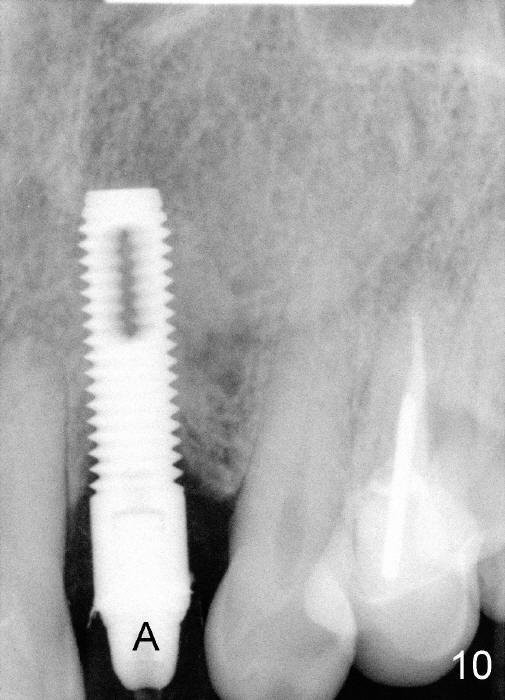

1. Place implant as lingual and apical as possible, cosmetic